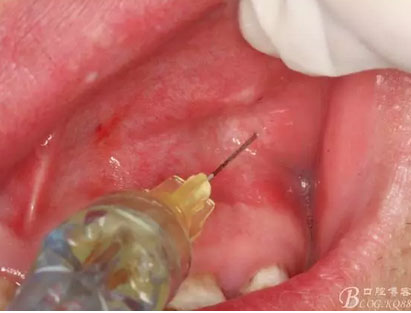

圖5.唇側(cè)局部無(wú)痛浸潤(rùn)麻醉